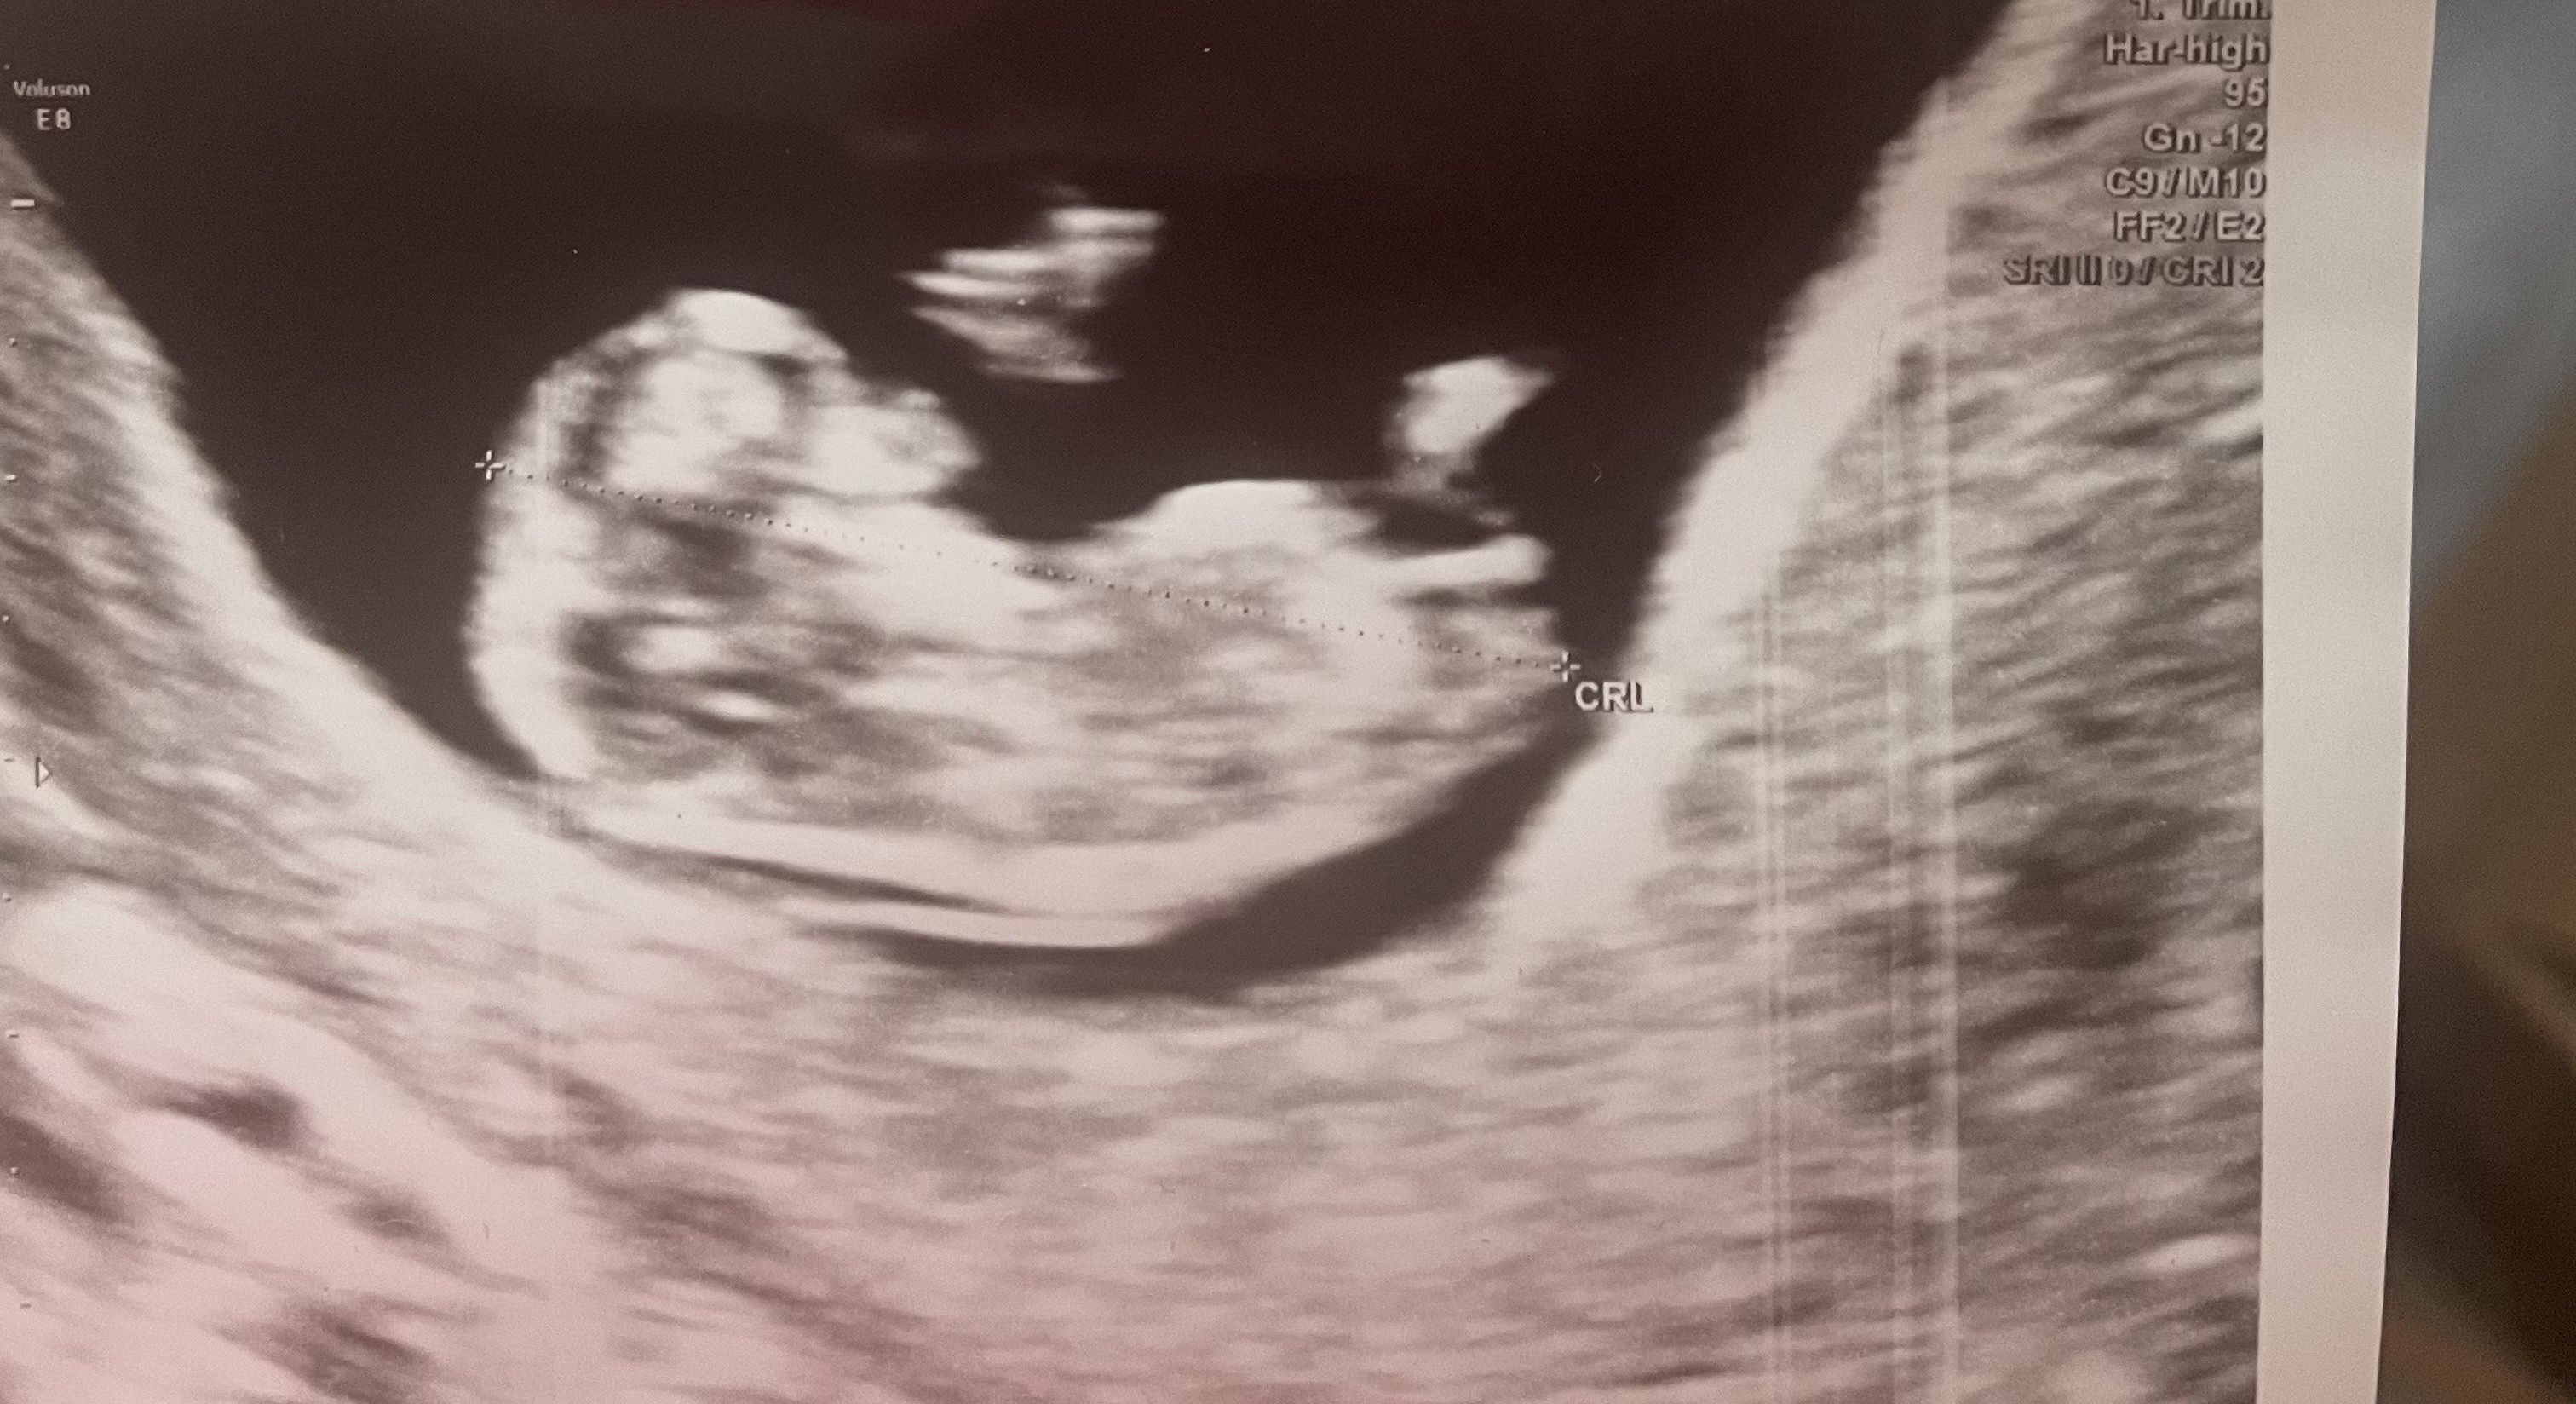

Witam, czy jesteście w stanie napisać po tym usg jaka będzie płeć?

Wyrostek widać ale ja tam się nie znam